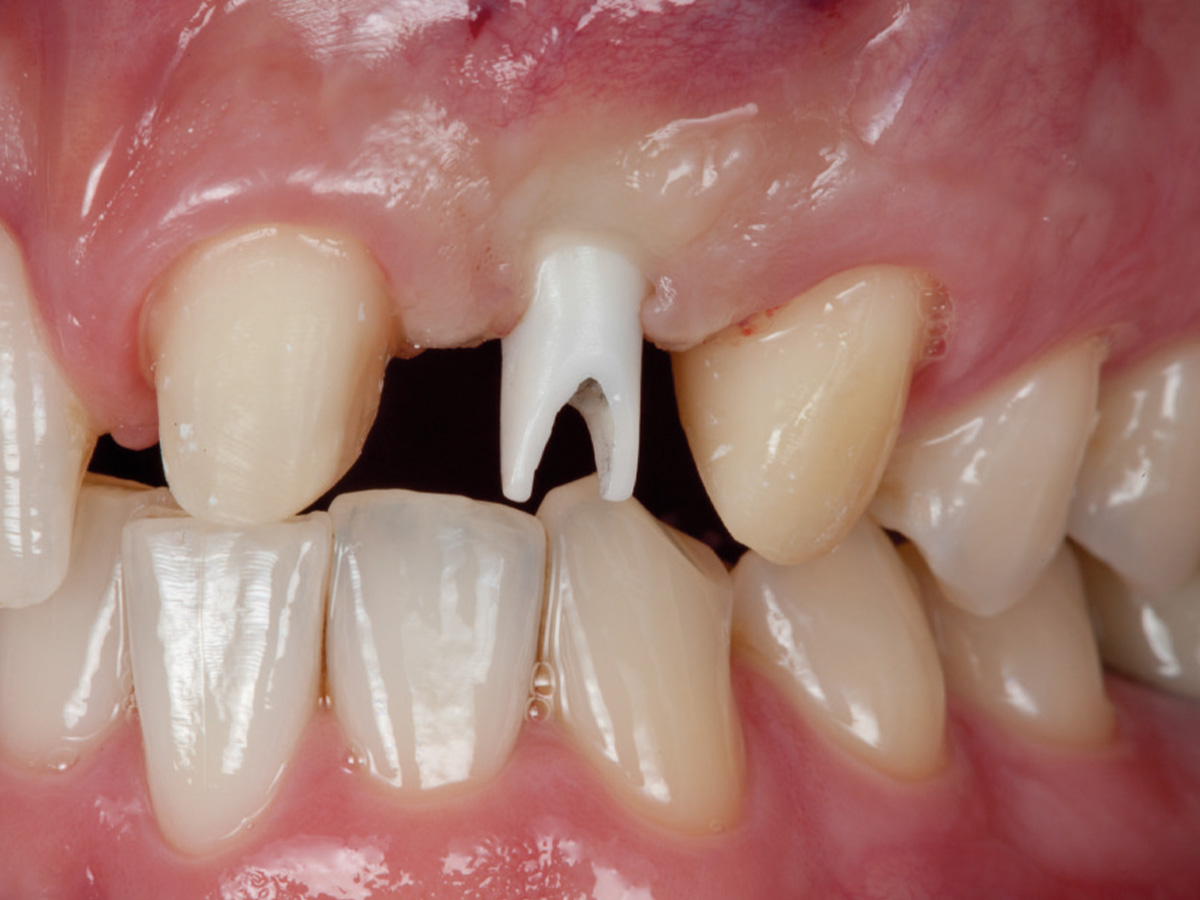

Abbildung 12

Regenerierter Alveolarkamm vor der prothetischen Versorgung.